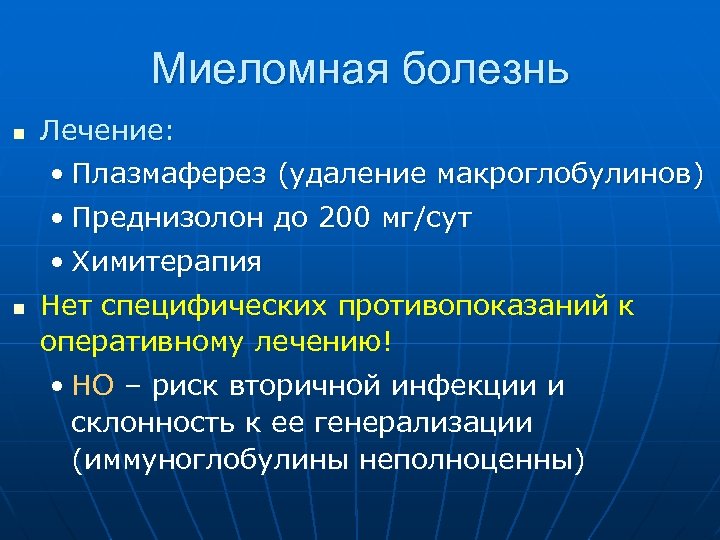

Миеломная болезнь n n Онкогематология • Плазматические (миеломные) клетки • Разрушение костей, патологические переломы • Гиперпродукция иммуноглобулинов (A, G, E, M) Тромбоцитопатия • Нарушение агрегации тромбоцитов • Геморрагические синдром, тяжелая анемия Нефропатия, уремия • Поражение почек парапротеинами и кальцием • Гиперкальциемическая кома Склонность к инфекционным осложнениям

Миеломная болезнь n Лечение: • Плазмаферез (удаление макроглобулинов) • Преднизолон до 200 мг/сут n • Химитерапия Нет специфических противопоказаний к оперативному лечению! • НО – риск вторичной инфекции и склонность к ее генерализации (иммуноглобулины неполноценны)